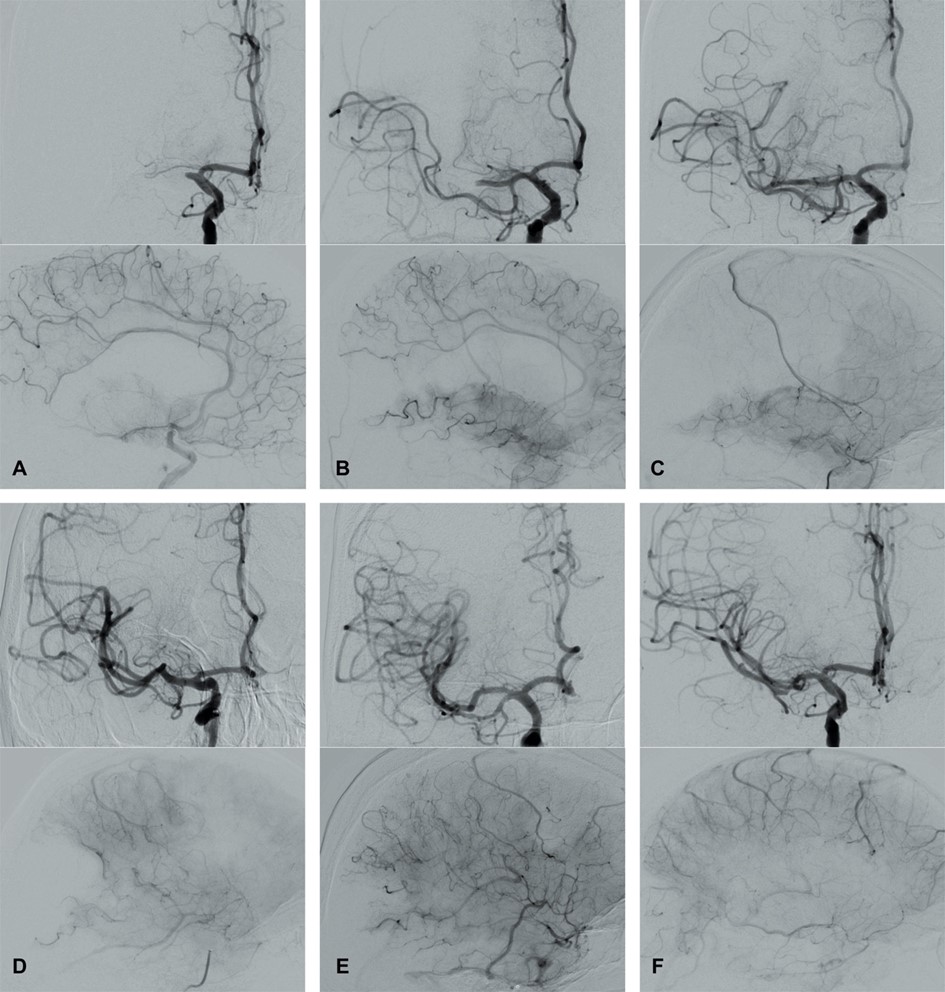

Fig. 1.ASPECTS. Visualization of the ASPECTS territories (A,B). The following areas are covered: M1 (anterior MCA cortex, frontal operculum), M2 (anterior temporal lobe, laterally to the insula), M3 (posterior temporal lobe, posterior MCA cortex), M4 (anterior MCA cortex superior to M1), M5 (lateral MCA cortex superior to M2), M6 (posterior MCA cortex superior to M3), insula (I), internal capsule (IC), caudate (C), and lentiforme nucleus (L). Each area accounts for 1 point. The maximum ASPECTS score is 10. Hypodensity in a described area leads to a deduction of one point. (C,D) show an example of CT ASPECTS. Hypodensity in the M2 and M6 areas is observed. Total ASPECTS: 8.